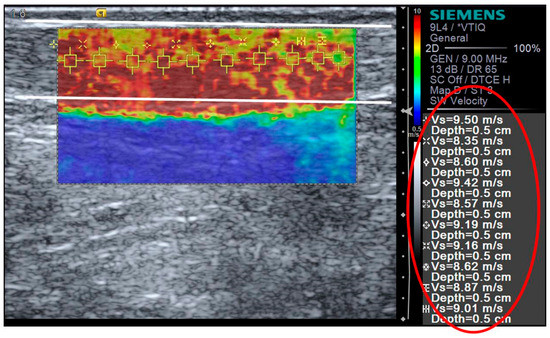

2.5. Shear Wave Elastography

| RUN SWV (m/s) | 9.16 ± 0.39 | 9.43 ± 0.39 | 9.00 ± 0.42 | 9.19 ± 0.31 | 9.04 ± 0.36 | 9.05 ± 0.28 |

| CONT SWV (m/s) | 9.11 ± 0.23 | 9.08 ± 0.22 | 9.04 ± 0.26 | 9.05 ± 0.22 | 9.06 ± 0.21 | 9.09 ± 0.22 |